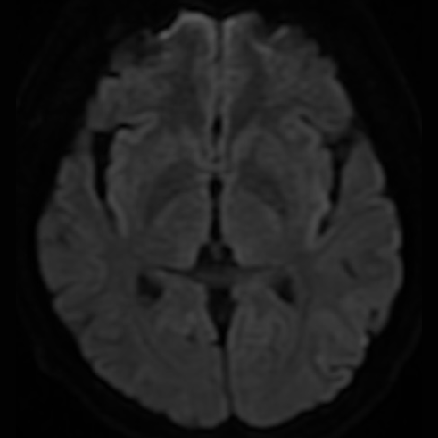

DSA提示患者右侧大脑中动脉狭窄率约95%;PWI提示右额颞顶叶低灌注。

动脉长鞘怎么置入一技之“长”丨经桡及经股困难入路应用赛诺神畅APEX TRA GC™导引导管建立通路病例合集_https://www.jmylbn.com_新闻资讯_第26张

头颅CT

动脉长鞘怎么置入一技之“长”丨经桡及经股困难入路应用赛诺神畅APEX TRA GC™导引导管建立通路病例合集_https://www.jmylbn.com_新闻资讯_第27张

头DWI

动脉长鞘怎么置入一技之“长”丨经桡及经股困难入路应用赛诺神畅APEX TRA GC™导引导管建立通路病例合集_https://www.jmylbn.com_新闻资讯_第28张

头MRI

动脉长鞘怎么置入一技之“长”丨经桡及经股困难入路应用赛诺神畅APEX TRA GC™导引导管建立通路病例合集_https://www.jmylbn.com_新闻资讯_第29张

头MRA

头PWI

DSA